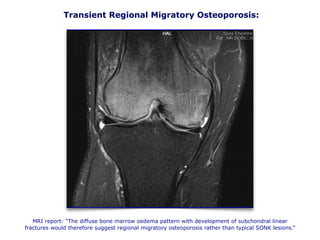

Transient Regional Migratory Osteoporosis:

MRI report: “The diffuse bone marrow oedema pattern with development of subchondral linear

fractures would therefore suggest regional migratory osteoporosis rather than typical SONK lesions.”

Transient Osteoporosis – Extreme Bone Remodeling?

• The aetiology of TO and TRMO remains unclear:

• One of the likely explanations for the pathogenesis of TO is

perhaps that proposed by Frost and others.

• He stated that under noxious tissue stimuli, the ordinary

biological processes, including blood flow, cell metabolism

and turnover and also tissue modelling and remodelling, might

be greatly accelerated, called the Regional Acceleratory

Phenomenon (RAP). In his opinion a prolonged or exaggerated

RAP in which a large number of bone turnover foci are activated,

is the cause of TO.

• It has been hypothesized that symptoms may be related to bone

marrow edema demonstrated at MRI and to a transitory regional

arterial hyperflow observed at the early scintigraphic analysis.

Bone tissue micro damage is the most frequent noxious

stimulus that provokes RAP and bone tissue micro

fracture is the main consequence.

• Several elements support this hypothesis. The repeatedly

observed histological findings in patients with TO showing mild

inflammatory changes and osteoporosis, associated with an

elevated bone turnover with increased bone resorption

and reactive bone formation are a good description of

ongoing TRMO.